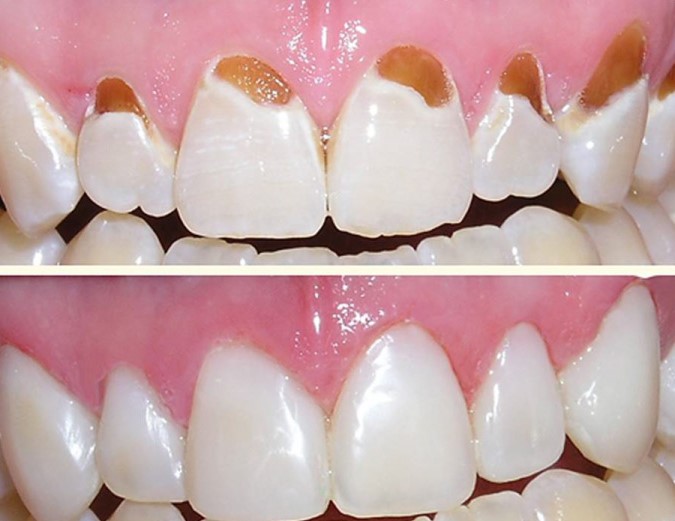

- Sâu răng.

- Răng bị gãy hoặc mẻ.

- Mòn men cổ răng.

- Răng bị ngả màu.

| Hàn/trám răng thẩm mỹ LASER TECH, tái tạo thân răng. | Răng | 500.000 |

| Hàn răng thẩm mỹ vỡ, mẻ. | Răng | 500.000 |